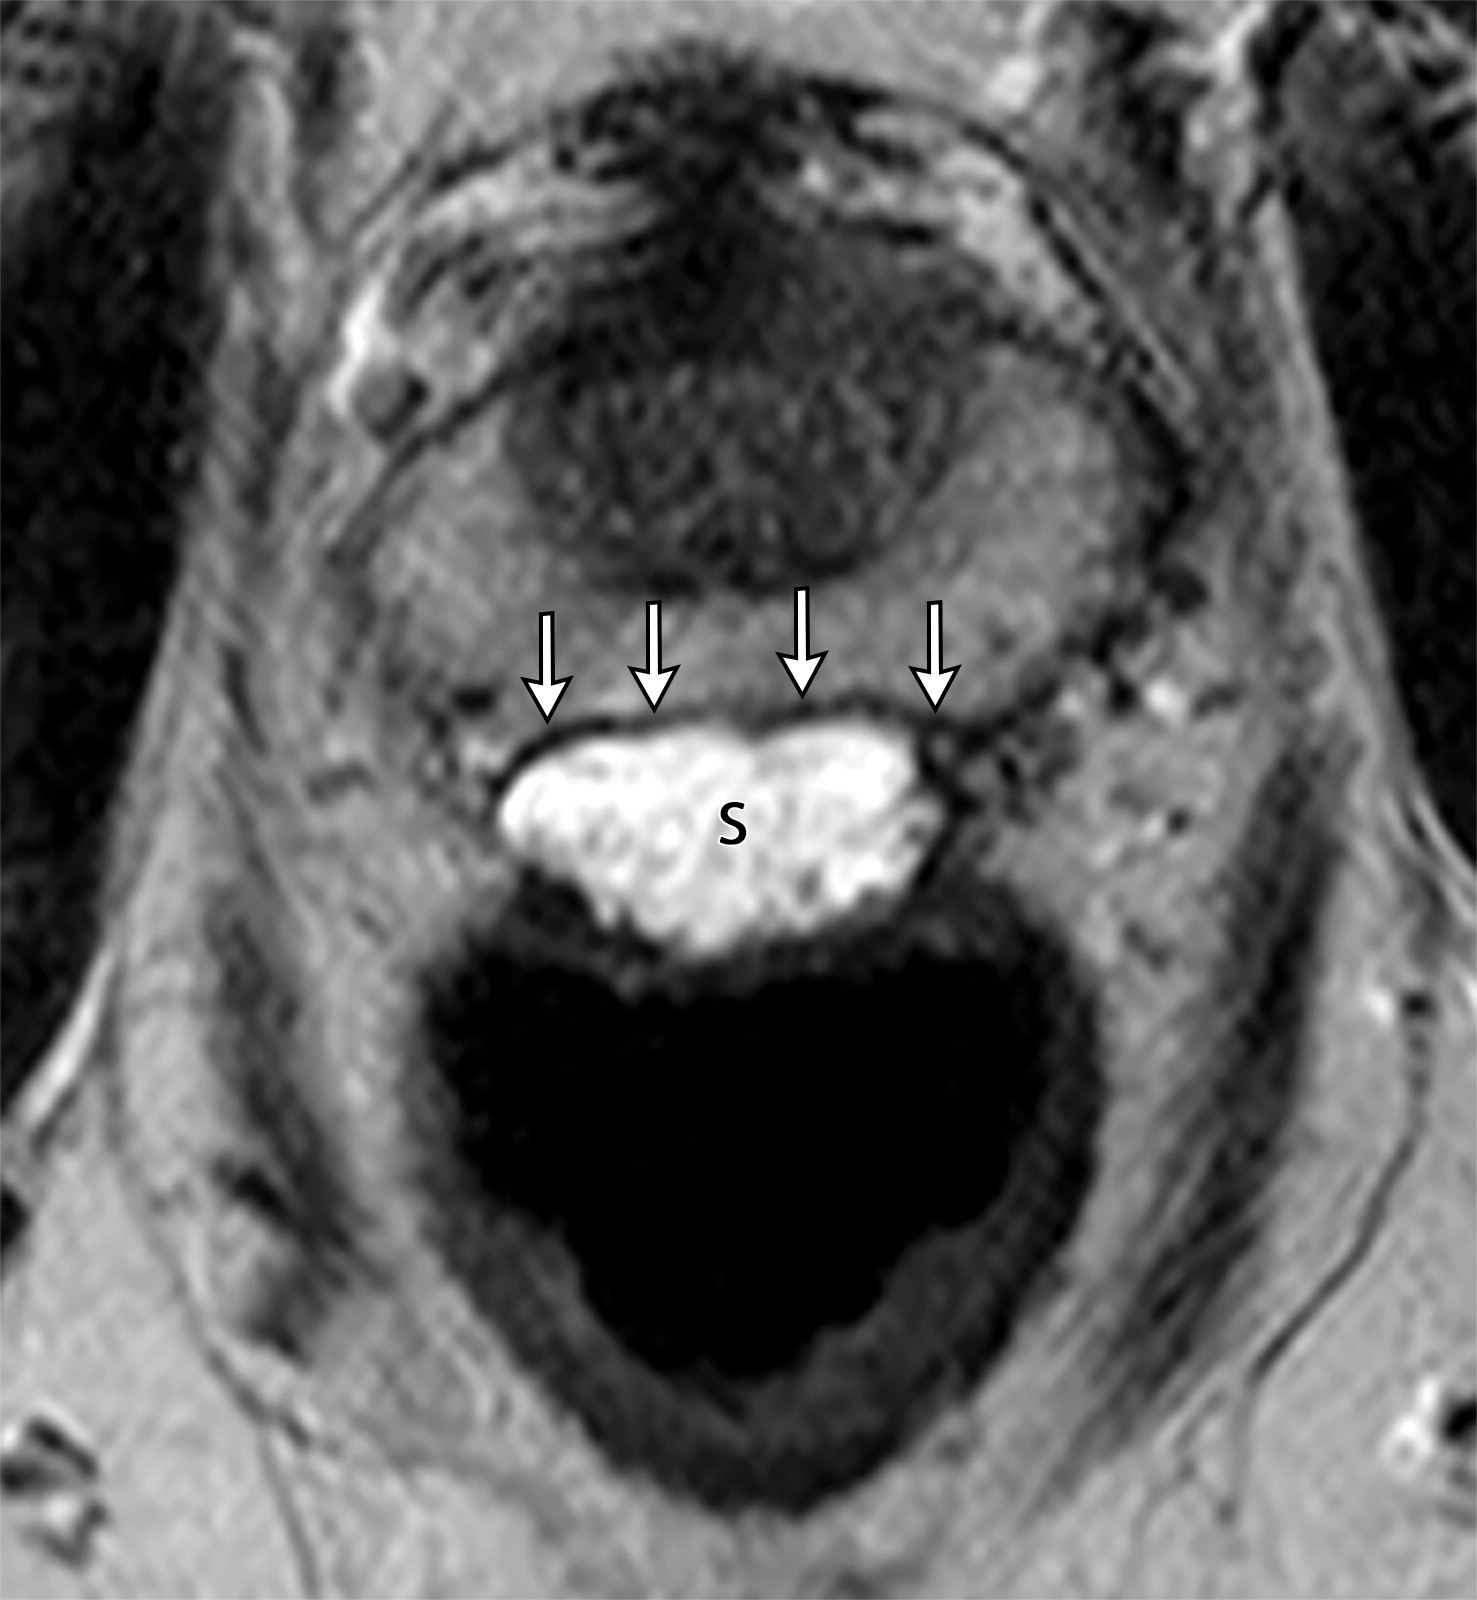

在Denonvillier筋膜和直肠后壁之间注射垫片的成功案例和失败案例。

(上图)成功案例,垫片(上图中黑色字母S)位于Denonvillier筋膜(上图中白色长箭头)与直肠壁之间,用于减少前列腺放疗的毒性作用。

(下图)失败案例,垫片位于前列腺周围血管(白色短箭头),这是当垫片注射至Denonvillier筋膜前方的时候(下图白色虚线点)一种潜在的并发症。